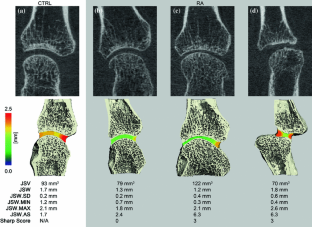

In this technique development study, high-resolution peripheral quantitative computed tomography (HR-pQCT) was applied to non-invasively image and quantify 3D joint space morphology of the wrist and metacarpophalangeal (MCP) joints of patients with rheumatoid arthritis (RA). HR-pQCT imaging (82 μm voxel-size) of the dominant hand was performed in patients with diagnosed rheumatoid arthritis (RA, N = 16, age: 52.6 ± 12.8) and healthy controls (CTRL, N = 7, age: 50.1 ± 15.0). An automated computer algorithm was developed to segment wrist and MCP joint spaces. The 3D distance transformation method was applied to spatially map joint space width, and summarized by the mean joint space width (JSW), minimal and maximal JSW (JSW.MIN, JSW.MAX), asymmetry (JSW.AS), and distribution (JSW.SD)—a measure of joint space heterogeneity. In vivo precision was determined for each measure by calculating the smallest detectable difference (SDD) and root mean square coefficient of variation (RMSCV%) of repeat scans. Qualitatively, HR-pQCT images and pseudo-color JSW maps showed global joint space narrowing, as well as regional and focal abnormalities in RA patients. In patients with radiographic JSN at an MCP, JSW.SD was two-fold greater vs. CTRL (p < 0.01), and JSW.MIN was more than two-fold lower (p < 0.001). Similarly, JSW.SD was significantly greater in the wrist of RA patients vs. CTRL (p < 0.05). In vivo precision was highest for JSW (SDD: 100 μm, RMSCV: 2.1%) while the SDD for JSW.MIN and JSW.SD were 370 and 110 μm, respectively. This study suggests that in vivo quantification of 3D joint space morphology from HR-pQCT, could improve early detection of joint damage in rheumatological diseases.

Figure 1